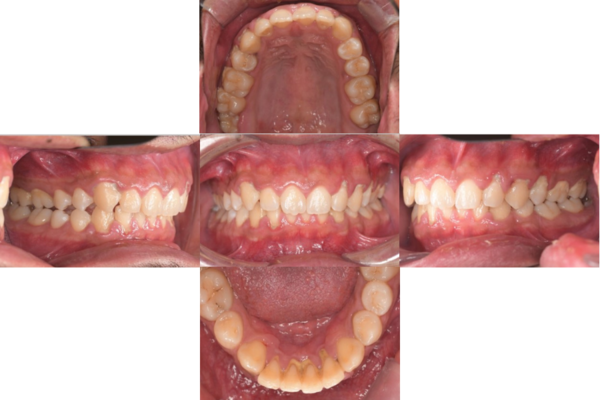

症例3

来院2回目、TBI後

症例

SRP後

初診時、TBI前

基本情報

年齢・性別 27歳・男性

主訴 主訴:左右下の歯ぐきに違和感がある

治療部位:全顎

治療内容 1.歯周基本検査、レントゲン撮影、口腔内写真、歯磨き指導、歯石除去、着色除去

2.SRP(スケーリングルートプレーニング)、再評価

その他

3.親知らずの抜歯

4.カリエス処置:右上1.2.3左上1.2.3右下6左下7CR(レジン充填)、右下7セラミックIn

5.定期検診

治療期間 6ヶ月

治療費 ※歯周基本治療の費用:PMTC以外保険診療3割負担

合計:19,680円

1.初診検査(歯周ポケット検査.レントゲン撮影):3,010円

2.歯磨き指導、歯面の歯石除去:1,410円

3.PMTC(自由診療):5,500円

4.SRP(歯周ポケット内の歯石除去)×4回:約2,000円/回

5.再評価:1,760円

(2023年12月現在)

リスク・副作用 ・最初は歯磨きをすると歯ぐきから出血するが毎日ホームケアを続けることで出血が徐々になくなる

・歯ぐきが腫れている状態が改善されると歯ぐきが引き締まり退縮するため、歯ぐきが下がったように感じることがある

・歯ぐきが引き締まると歯間が開いたように感じることがある

・歯ぐきが引き締まると知覚過敏の症状がでる可能性がある

・一度歯石を除去しても毎日のホームケアを怠ると再度歯石がつく

・治療後も再発を防ぐために定期的なメインテナンスが必要である

治療方針 1.初診検査(レントゲン撮影、口腔内写真、歯周検査、歯磨き指導)

2.歯磨きチェック、歯石除去、PMTC

3.SRP

4.再評価

特記事項 ・歯科医院は今回初めて

・タバコは24歳まで3年ほど吸っていたが健康のためにやめた

・親知らずは右下以外抜歯

・歯ブラシはルシェロP20M、補助用具はフロスを処方

担当者所見 全体的に歯と歯ぐきの境目に歯垢(細菌の塊)が残り、日々のホームケアで落とし切れていなかったことと、歯科医院への定期検診の習慣がなかったことから、全顎的な歯肉炎になってしまったと考えられる。

歯周基本治療とホームケアで歯ぐきの腫れや歯周ポケット、出血率などかなり改善されたが、出血がまだ0%ではない為、引き続き歯ブラシの当て方をお伝えしつつ今後は定期検診で3ヶ月おきに再発しないよう一緒に管理していく。